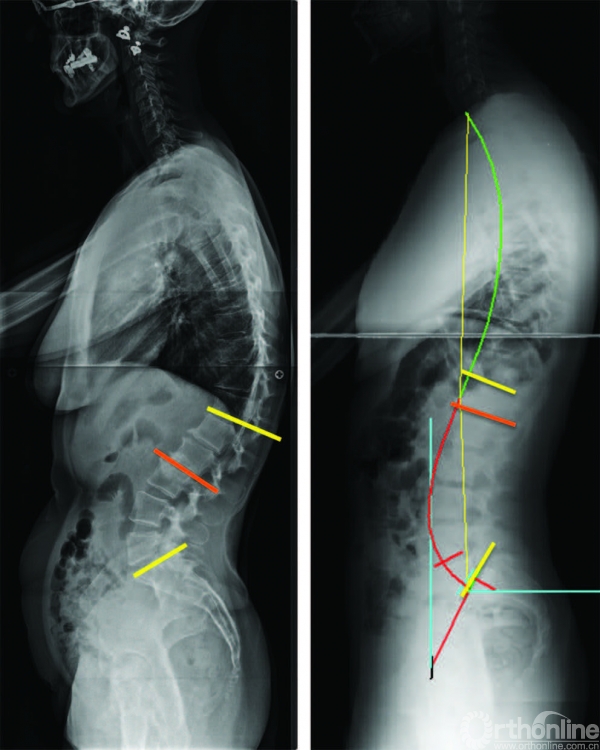

图 6-6 全脊柱侧位X线

片中前凸长度的影响在左侧,有一个短节段腰椎前凸,前凸主要集中在少数几节脊椎。注意前凸曲线的上端在L3。在右边,有一个较长节段的腰椎前凸

在脊柱的功能性分界中,腰椎前凸和胸椎后凸的界限是基于脊柱的各个矢状面形状。换句话说,腰椎前凸的上端椎不应该固定在L1,而应与脊柱侧弯的冠状Cobb角类似,从骶骨上终板到上端椎(图6-6)[11]。腰椎前凸跨越脊椎,从骶骨上终板到胸椎后凸开始的临界点。同样,胸椎后凸跨越脊椎,从腰椎前凸的临界点到颈椎前凸的临界点。

脊柱曲度的分析还包括其他概念。Berthonnaud[10]等认为一段圆弧(如腰椎前凸)可被其顶点分成两段,过这一顶点作一条水平线(图6-7)。每个圆弧的半径和长度是独立的,由两个重要的点来决定:曲线的顶点和临界点(图6-7)。

因此,腰椎前凸的上弧位于腰椎前凸顶点和上临界点之间,腰椎前凸下弧位于其顶点和骶骨终板之间。同样,胸椎后凸被分为两段弧:上弧和下弧。胸椎后凸的上弧位于其顶点和颈椎前凸的临界点之间。胸椎后凸的下弧位于其顶点与临界点(腰椎前凸和胸椎后凸之间的临界点)之间。

图 6-7 腰椎前凸的下弧角(SL)与骶骨倾斜角(SS),以及腰椎前凸上弧角与胸椎后凸角之间的几何关系

后凸和前凸之间临界点的位置、前后凸顶点的位置及腰椎前凸下弧角的弯曲度是决定矢状面形态的重要因素